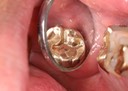

Matt Dodson #15 pre-op

Matt Dodson #15 amalgam removal